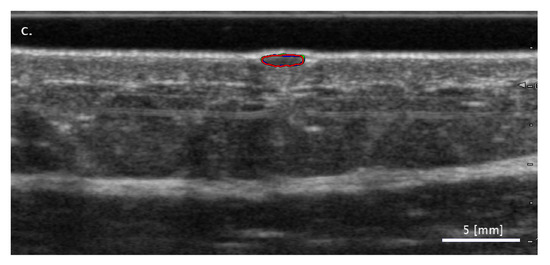

3.2.3. Cases When the SA Methods Both Fail While the FA Method Performs Correctly